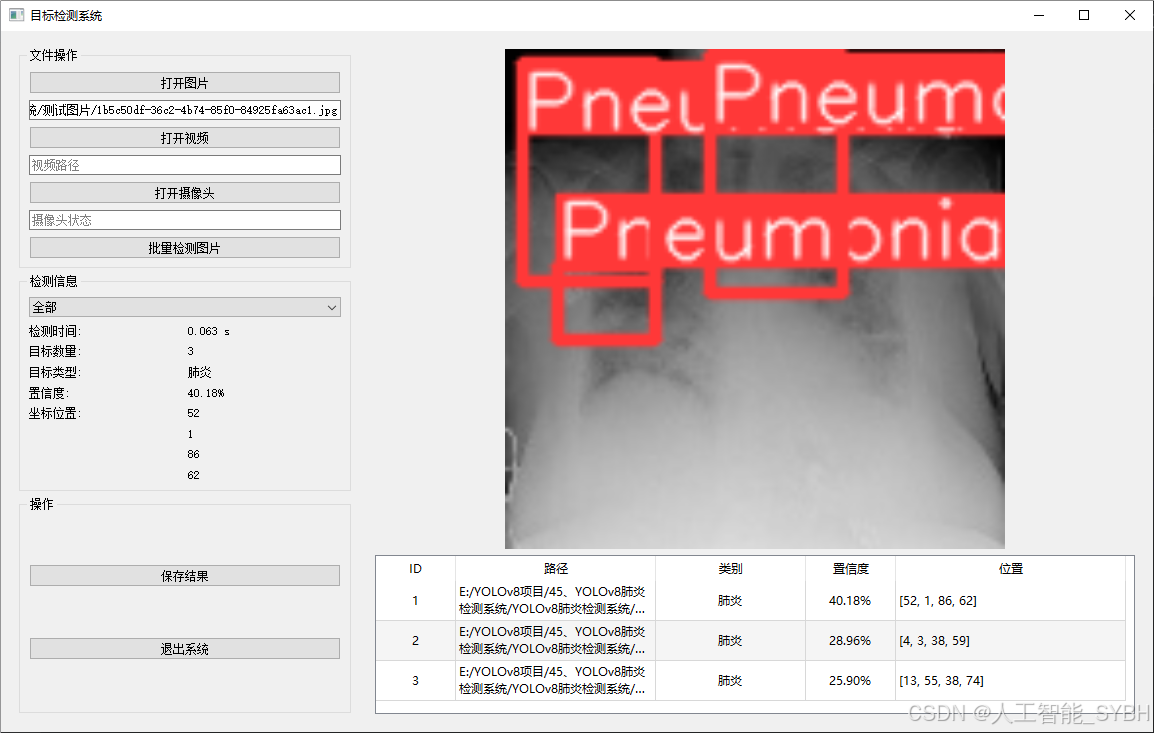

二、项目功能展示

系统功能

✅ 图片检测:可对单张图片进行检测,返回检测框及类别信息。

✅ 批量图片检测:支持文件夹输入,一次性检测多张图片,生成批量检测结果。

✅ 视频检测:支持视频文件输入,检测视频中每一帧的情况。

✅ 摄像头实时检测:连接USB 摄像头,实现实时监测,

图片检测

该功能允许用户通过单张图片进行目标检测。输入一张图片后,YOLO模型会实时分析图像,识别出其中的目标,并在图像中框出检测到的目标,输出带有目标框的图像。批量图片检测